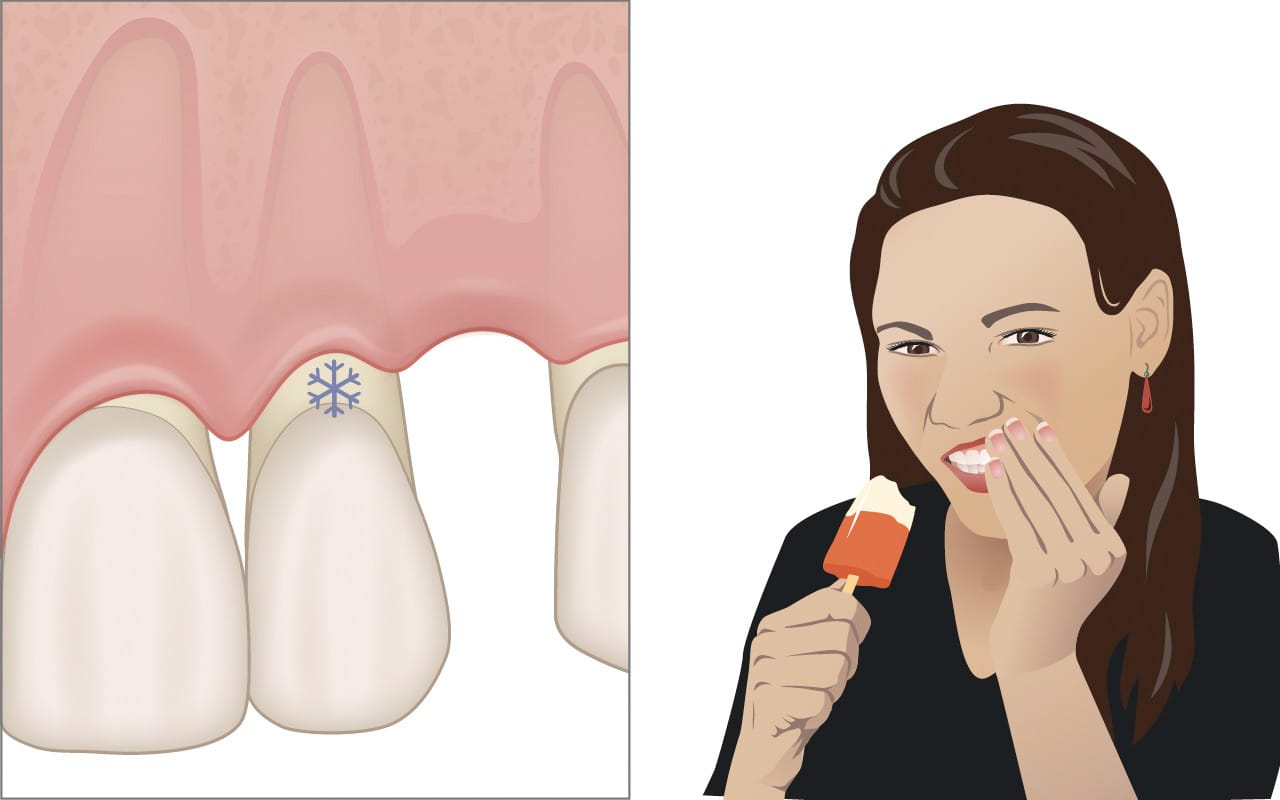

Après traitement, il peut apparaître :

Une légère rétraction gingivale

Une sensibilité temporaire au froid

Une ouverture des espaces interdentaires

Ces effets sont généralement transitoires.

La plupart des patients décrivent une gêne modérée et temporaire. Une légère sensibilité au froid peut apparaître après le traitement, mais elle diminue généralement en quelques semaines.